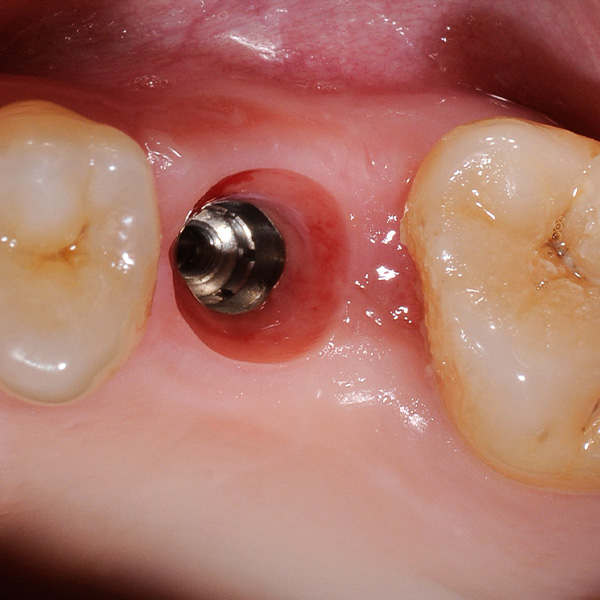

Restaurationen auf Implantaten sind besonders hohen Belastungen ausgesetzt. Da dem Patienten der elastische Faserapparat des natürlichen Zahnbetts fehlt, werden Kaukräfte nicht absorbiert, sondern direkt auf die Restauration, das Implantat, den Knochen sowie die Gegenbezahnung übertragen. Die Hybridkeramik VITA ENAMIC verfügt über eine duale Netzwerkstruktur aus Keramik und Polymer. Daraus resultieren eine dentinähnliche Elastizität und die Fähigkeit, Kaukräfte zu absorbieren. Der mehrfarbige Rohling VITA ENAMIC multiColor in der Geometrie EMC-16 ermöglicht aufgrund seiner hohen vertikalen Dimension auch bei atrophiertem Knochen die Herstellung einteiliger, monolithischer Abutmentkronen. Zahnarzt Professor Dr. Alexander Hassel zeigt im folgenden Beitrag, wie er eine Patientin mit dieser Restaurationsform versorgt.